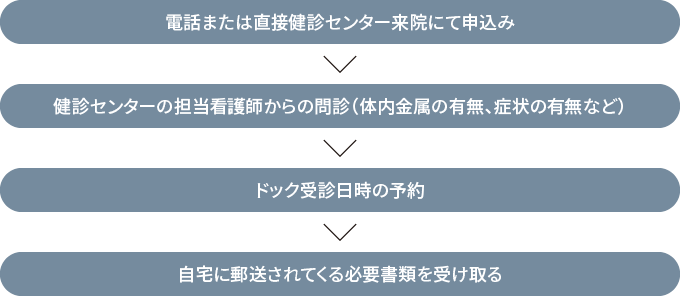

申し込みは下記にお電話いただくか、直接健診センターで受け付けております。

(申込み時に簡単な問診を行います)

電話:025-552-8835 健診センター 膵がん・胆道がんドック予約担当

(受付時間:午後1:00~午後4:00 *土日祝祭日を除く)